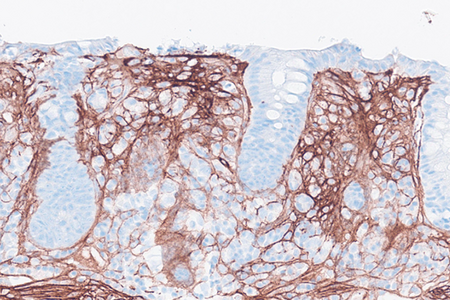

Histology of several colonic sites showed a thickened subepithelial collagen band (>10 μm), predominantly beneath the superficial epithelium but also surrounding the crypts (Panel A). Surface epithelial injury was also observed, with focal mucin depletion and detachment of superficial epithelial cells (Panel B). Lamina propria showed increased cellularity, with lymphocytic and plasmocytic infiltration, along with numerous giant cells (Panel C). There was no crypt architectural distortion. The collagen deposition was highlighted by Masson’s trichrome stain (Panel D) and strongly by tenascin immunohistochemistry (Panel E).

Histological variants of both collagenous and lymphocytic colitis have been described, including collagenous colitis with giant cells. In this variant, multinucleated giant cells are abundant and scattered throughout the lamina propria, with no apparent prognostic value.